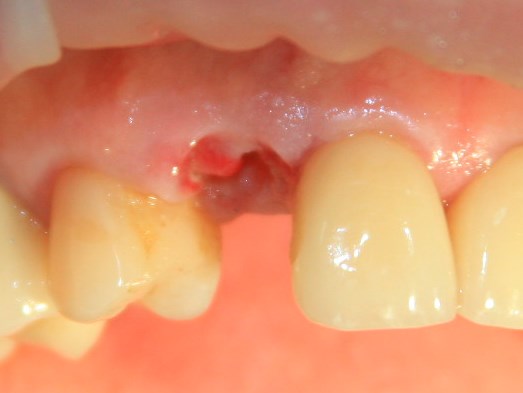

Немедленная имплантация — оптимальное решение в любой клинической ситуации